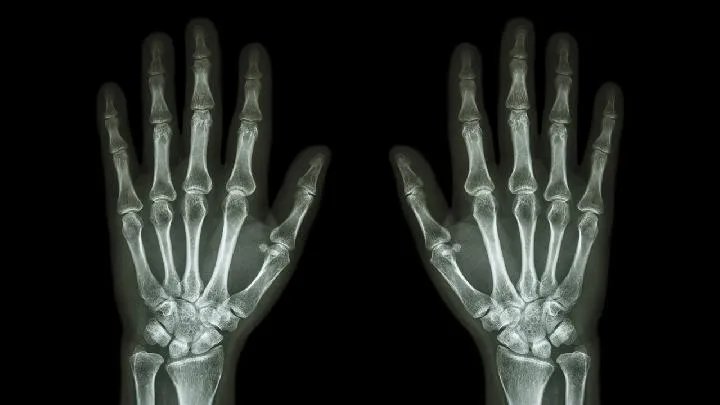

寒湿型

主要表现为关节肿痛或有积液,纳差,大便搪薄,小便清长,畏寒,舌淡苔白腻,脉濡,血沉也增快。此型的患者应选用一些温热性的食物,如 猪、牛、羊骨头煮汤,及姜、桂皮、木瓜、药酒等。因为酒性辛热,助阳生火,能祛散寒邪,可饮用一些药酒类的酒剂。对于一些不会饮酒的病人,可以稀释或加入 调料调味后饮用。

肝肾两虚型

这型患者可表现为关节疼痛畸形,肌肉萎缩,筋腱拘挛,畏寒,消瘦,面色无华,舌淡苔薄白或白腻,脉沉细,而血沉多不增速,或接近正常。此型患者可以多食一些补益的食品,如甲鱼肉、鸡肉、鸭肉、鹅肉、猪肉、牛肉、羊骨髓、胡桃、桂圆、芝麻等。